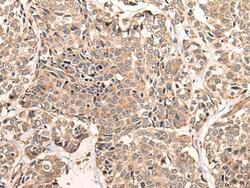

- Immunohistochemistry of paraffin-embedded Human esophagus cancer tissue using LDAH Polyclonal Antibody at dilution of 1:55(×200)